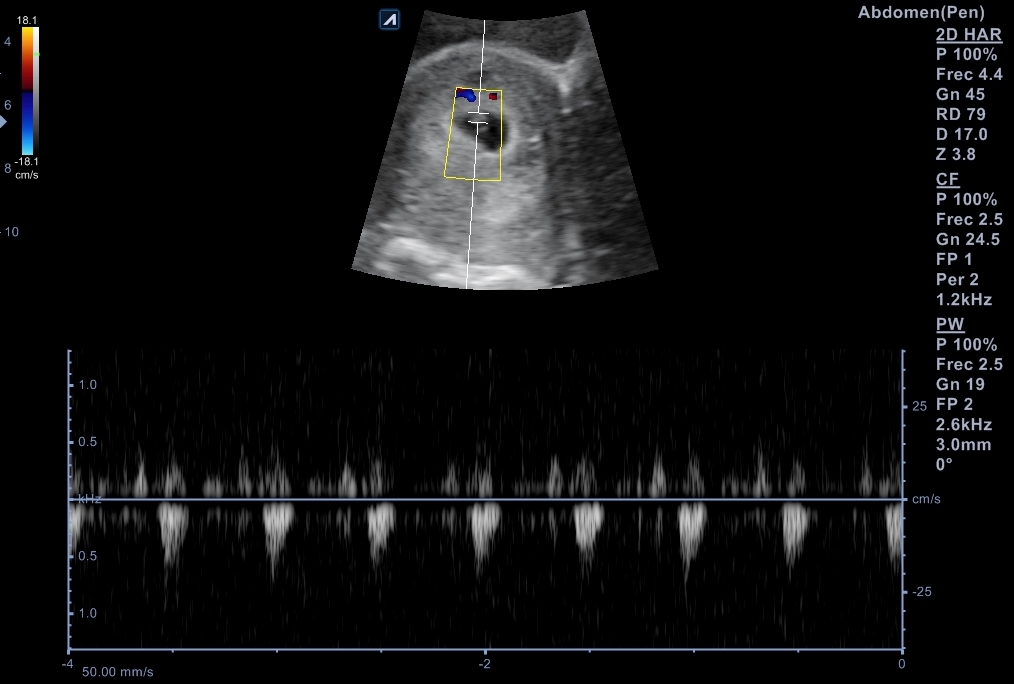

Se explora pelvis con sonda cónvex: vejiga distendida de paredes lisas y homogéneas. Útero en anteversión con endometrio decidualizado y saco embrionario en su interior, bien posicionado con una estimación de 6 + 2 semanas de gestación. Se localiza cuerpo lúteo en anejo izquierdo que, además está aumentado de tamaño.

Nueva ecografía: saco embrionario con embrión con latido fetal a 135 lpm y se data de 6 + 4 semanas. Se cita para analítica de primer trimestre, así como con Obstetricia.